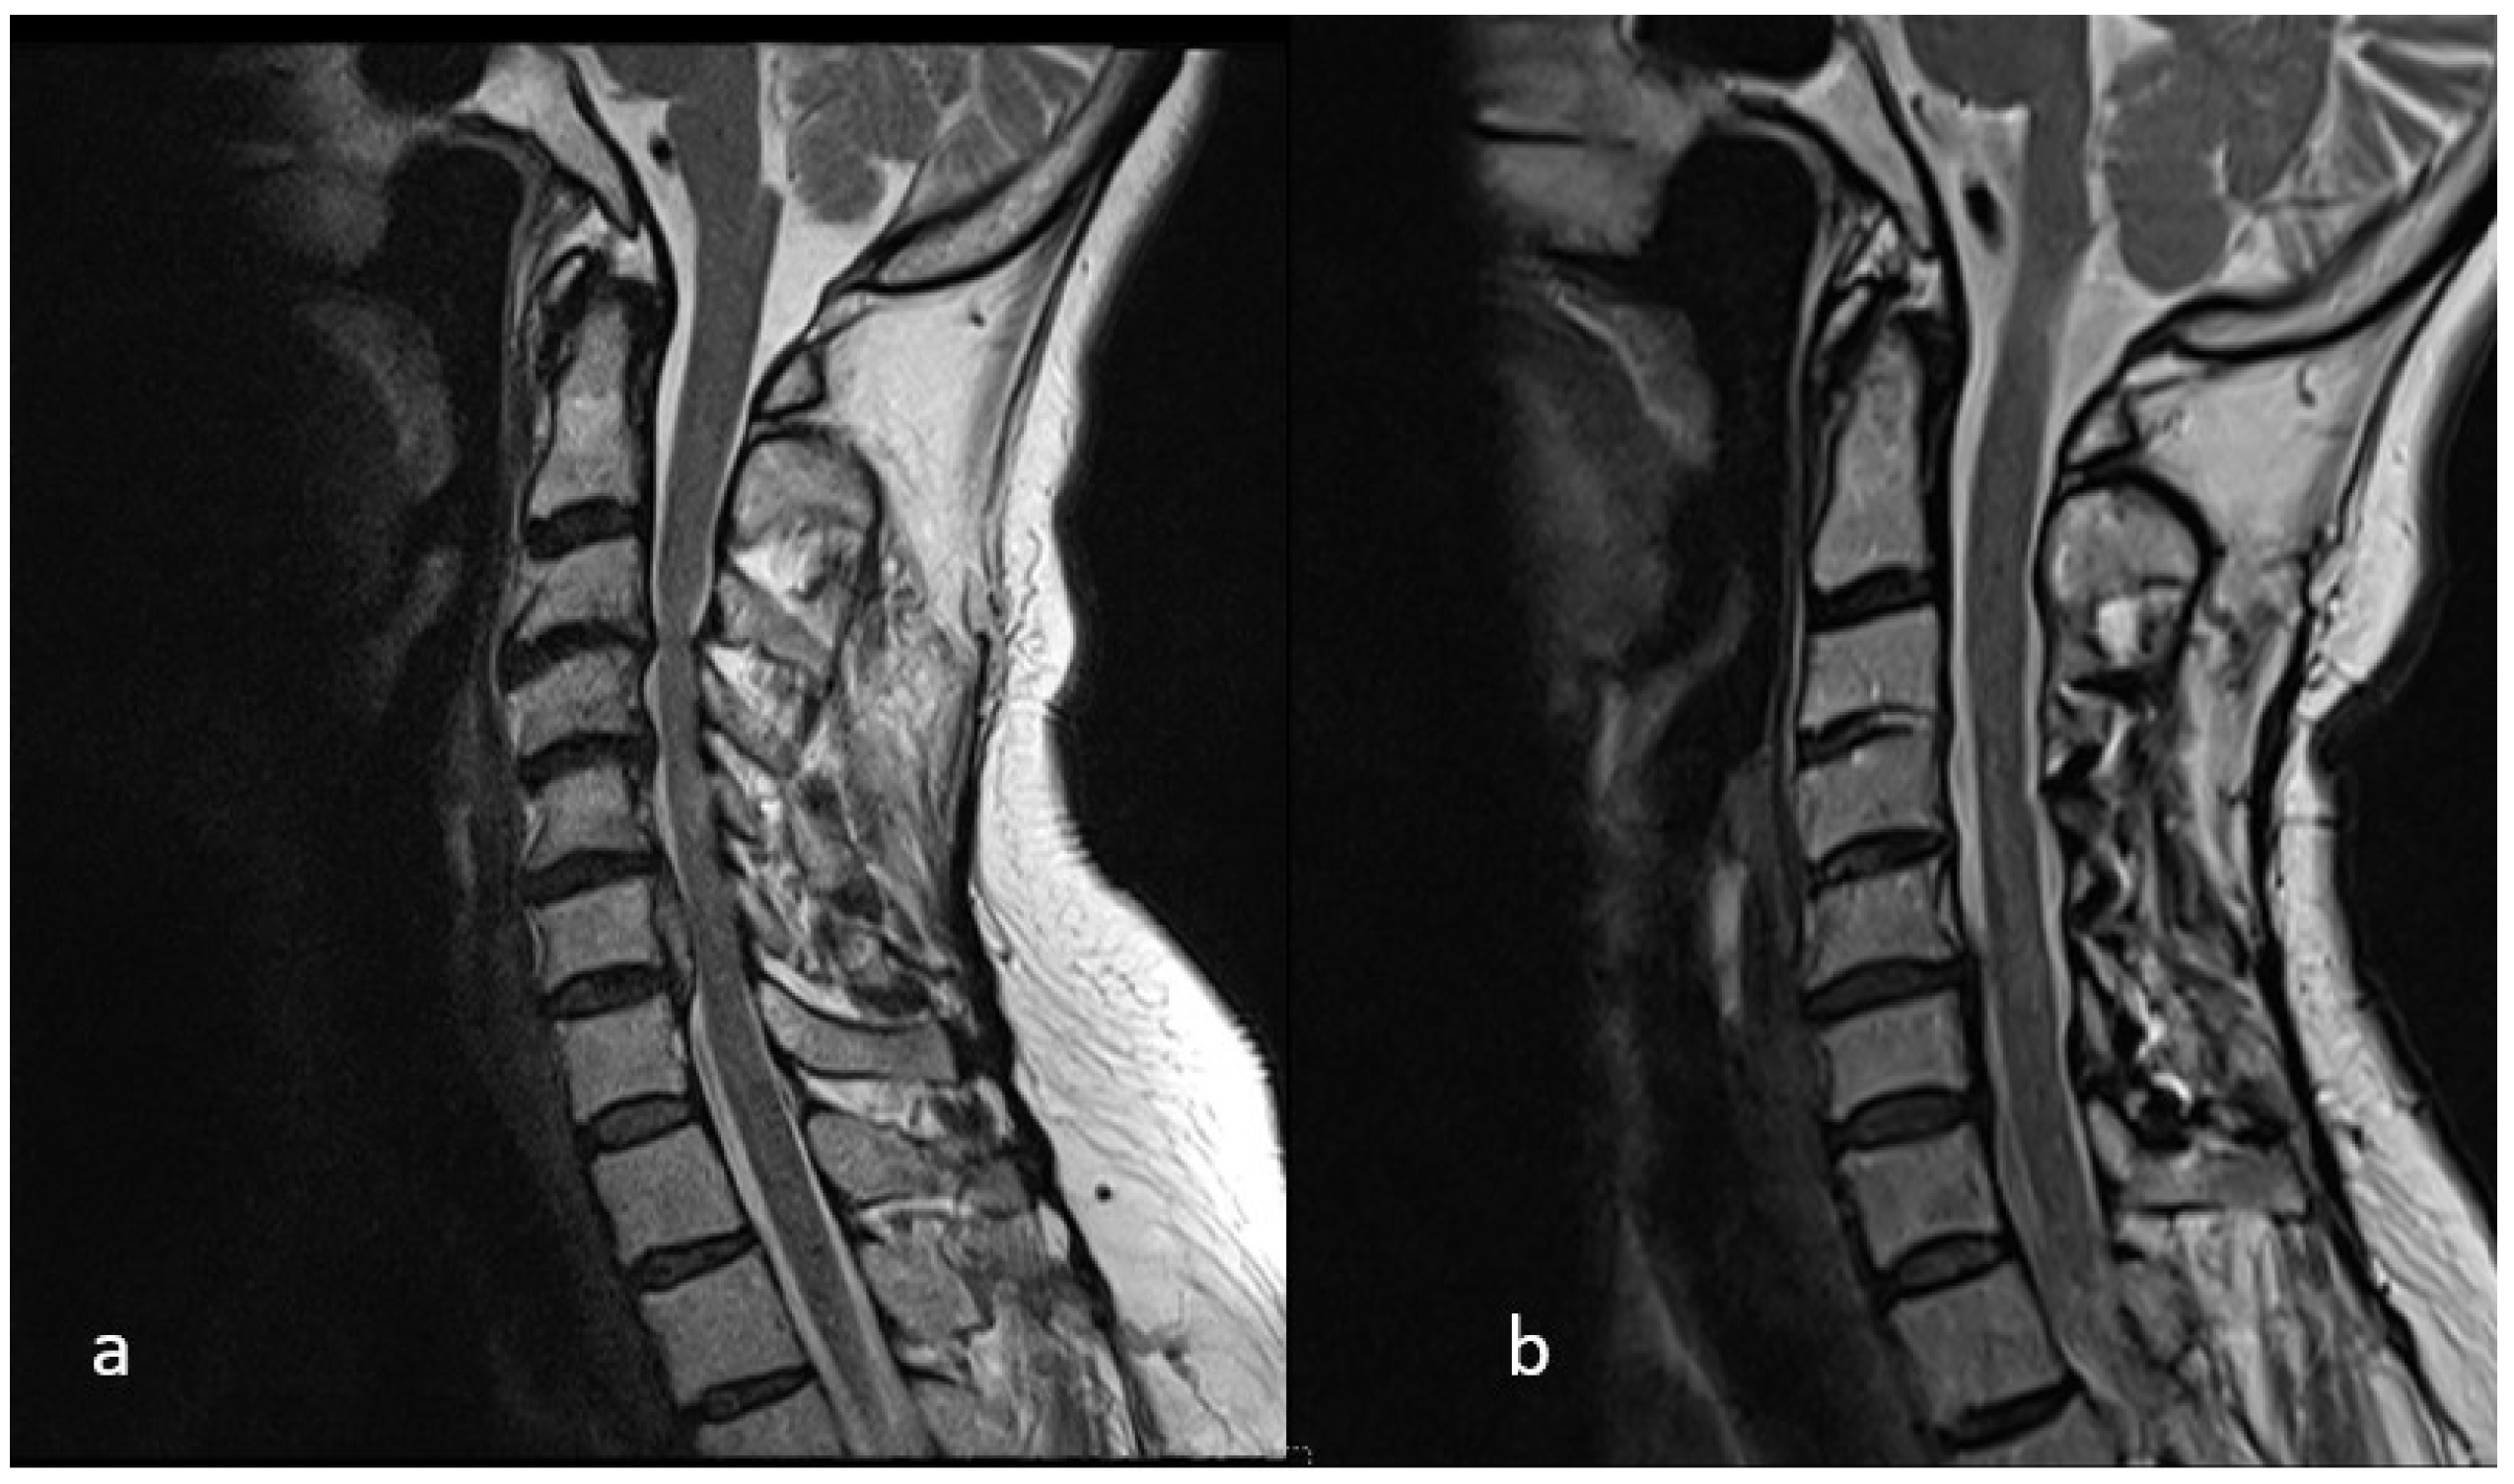

Preoperative Cervical Alignment Category vs. Postoperative Cervical Alignment Category

Preoperative K-Line vs. Postoperative K-Line

4. Discussion